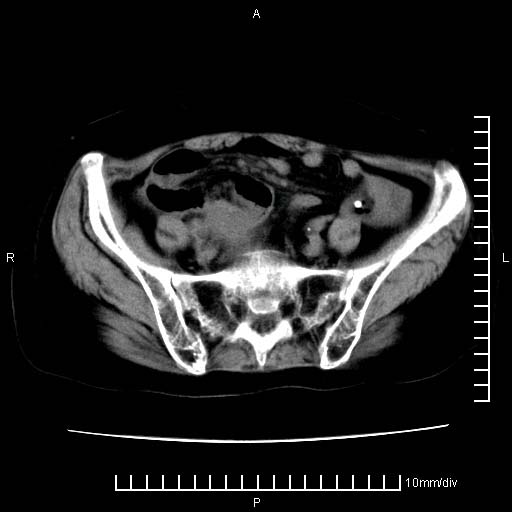

下腹疼痛2月,加重并呕吐2天,下腹压痛,反跳痛。白细胞1万2.

考虑卵巢恶性肿瘤;盆腔积液。

来源于附件占位—多考虑:卵巢癌

有病理了,楼上的哥们你说对了

感谢楼主反馈术后病理结果(卵巢癌),学习了!